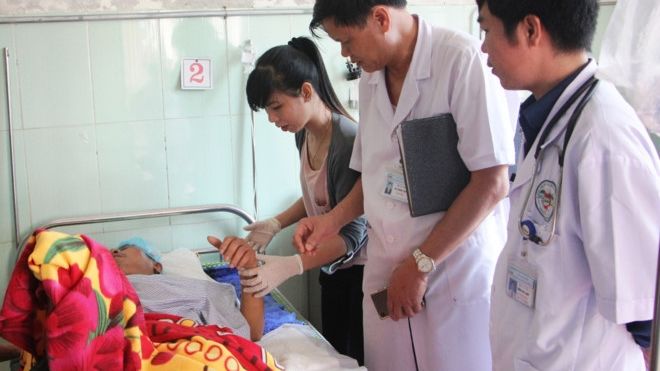

Thanh niên tử vong đột nhiên bừng tỉnh khi cả nhà đang lo hậu sự

Bệnh nhân 'sống lại' khi gia đình chuẩn bị hậu sự